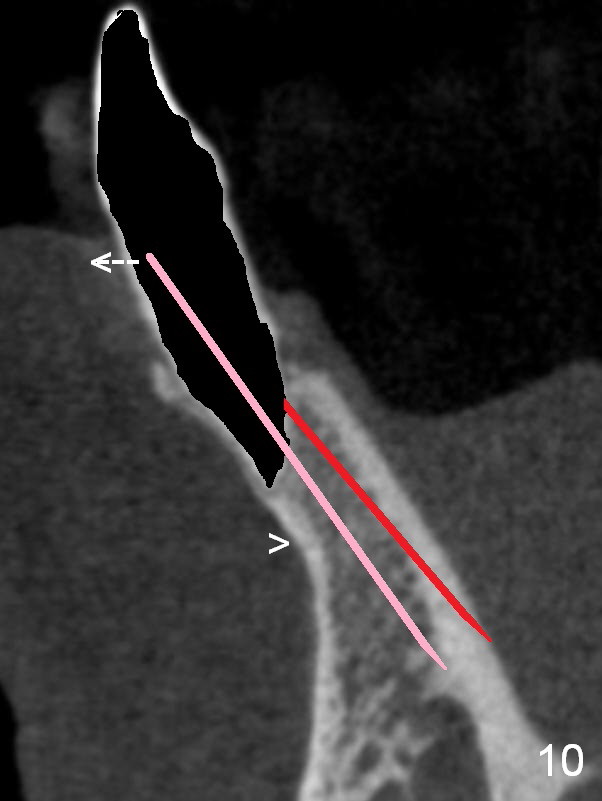

A 74-year-old man has several missing teeth (Fig.1).  His 1st goal is to replace the lower left lateral incisor (Fig.2).  The residual root has an apical lesion (Fig.3 *).  To describe intraop findings, a CT image of a different patient is used (Fig.4 coronal section; B: buccal; L: lingual).  After extraction, the buccal plate is found to be thin and low (Fig.5 arrowheads).  A 1.5 mm pilot drill (Fig.6 red line) is used to initiate osteotomy in the lingual plate of the socket.  Once the drill penetrates the lingual plate, the trajectory changes and the depth is 17 mm from the gingival margin (Fig.7).  A PA is taken (Fig.8); it appears that the osteotomy can be extended more apically.  When the pilot drill extends to 20 mm, there is sudden empty feeling.  The lingual plate has perforated (Fig.9).  A new osteotomy is established buccally (Fig.10 pink).  To avoid buccal plate perforation, especially in the buccal undercut area (>), the coronal end of the drill has to be tilted buccally (<--).  An angled abutment (3x20 mm, 15°) is placed (Fig.11,12).  The abutment is modified (Fig.13,14) to accommodate an immediate provisional (Fig.15,16 P).  Perio dressing is to be applied to prevent the bone graft from getting dislodged buccally (Fig.15).  The dressing is in place 7 days postop (Fig.17).